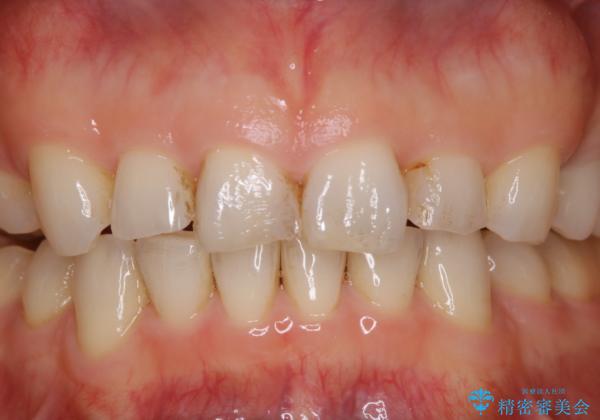

前歯のステイン(着色)をPMTCでキレイに

- コーヒーを普段からよく飲むため、着色・ステインが気になるとのことで来院されました。着色が前歯のみに付着していたためPMTC自費クリーニングの30分コースを行いました。

一か所茶色く色が残っている所がありますが、これは詰め物の変色です。

以前にCR(コンポジットレジン)による虫歯の治療での充填がされています。

CRは経年的に劣化や変色、着色がついてしまいます。

PMTCでしっかりとクリーニングを行うと、古いCRが目立つことがあり、気になる際は詰め替えを行います。